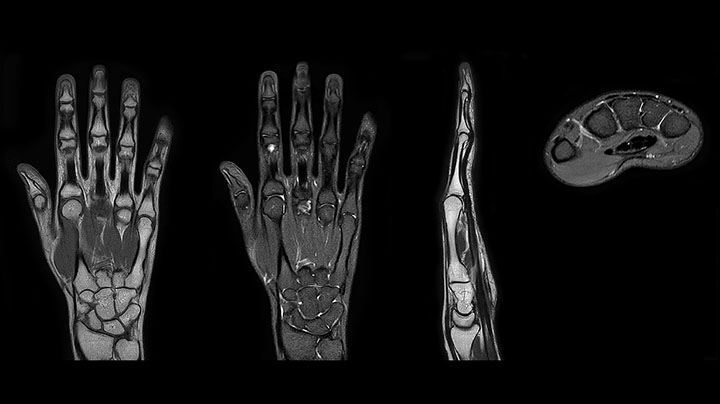

“The quality of the contrast-free MR angiography keeps impressing us,” says Mrs. Schiffer. “In addition to not having to inject contrast agent, these images are amazing, for instance of the carotids. Also our exams of shoulders and hands are really exceptional. Images of the hands, for example, cover the fingertips and include the full wrist as well, all with high signal-to-noise ratio.”

MRI of hand and wrist with large FOV

Prodiva imaging of the hand covers the fingertips and includes the full wrist as well. The dS MSK M coil is easy to use.

MRI of the finger

MRI of the finger with high SNR and good resolution in a 10 cm field of view on Prodiva 1.5T. The diagnosis in this 63-year-old patient is bone elasmanosis.